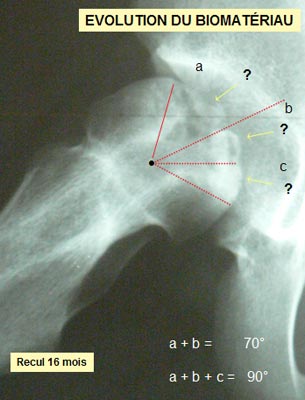

Que se passe t'il à l'intérieur de l'os ? Clichés comparatifs intermédiaires - A : L'IRMN avant la greffe de biomatériau montre l'étendue de la nécrose sur la hanche de face. - B : L'IRMN postopératoire à 10 mois précise l'étendue de la nécrose dans la tête fémorale « in situ ». - C : Les Rx standards pré et postopératoire à 16 mois précisent l'évolution de la nécrose. - D : Les Rx standards post - opératoire à J + 1 et à 16 mois précisent l'évolution du biomatériau. ETENDUE de la NÉCROSE

EVOLUTION de la NÉCROSE

Sur le plan radiographique : - La zone nécrotique est nettoyée. - L'aplatissement de la tête fémorale ne s'est pas aggravé depuis l'intervention. - le corail naturel est résorbé au niveau du col ; il est partiellement résorbé au niveau de la tête fémorale.